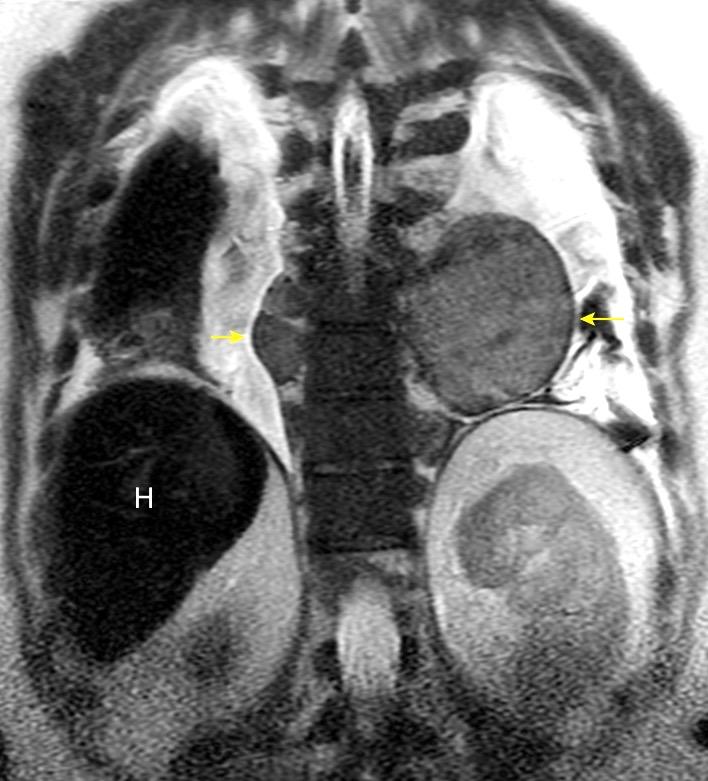

T. mixto de células

Ganglios retroperitoneales (flechas negras)

germinales del testículo izquierdo Nódulos pulmonares múltiples. (flechas verdes). Ganglios paratraqueales. (flechas amarillas). Dudoso ensanchamiento retrocrural (flechas negras)

Panda A et al. “Straddling Across Boundaries”. Thoracoabdominal Lesions: Spectrum and Pattern Approach. Curr Probl Diagn Radiol, 2015